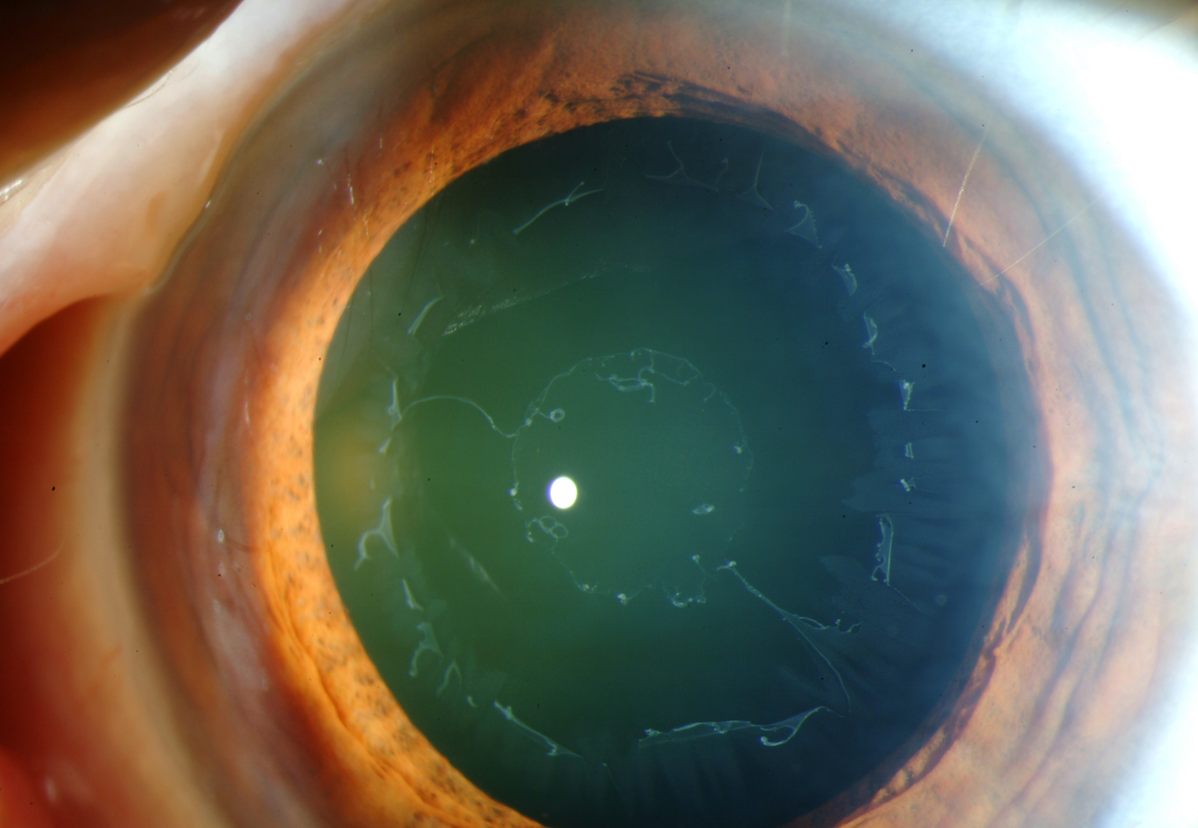

Pigmentary Dispersion Syndrome

- Mid-peripheral TIDs.

- Result of concave iris.

Pseudoexfoliation Syndrome

- Pupillary border TIDs.

- Causes zonulopathy.